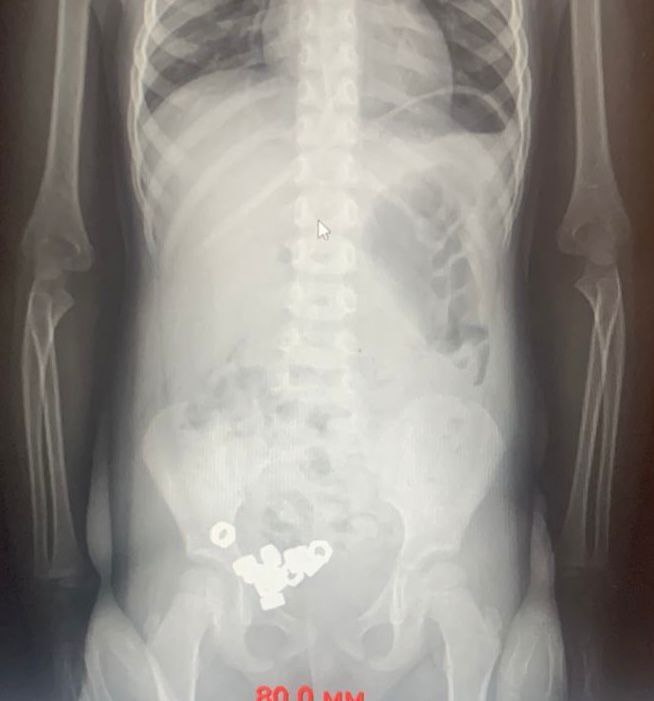

В Воронеже трехлетний малыш проглотил 16 гаек У 3 летнего ребенка воронежские врачи обнаружили в животе 16 гаек Малыша привели на прием в областную детскую больницу 2 родители предположили что мальчик проглотил инородные предметы Хотя никаких болезненных симптомов не испытывал Рентген брюшной полости действительно показал наличие множественных темных пятен в желудочно кишечном тракте ребенка Малыша госпитализировали чтобы исключить риск осложнений Инородные тела были не магнитные поэтому врачи выбрали консервативную тактику назначили диету покой контроль стула и рентгенографию в динамике К третьему дню все инородные тела успешно вышли естественным путем Оказалось что ребенок проглотил 16 гаек Малыша уже выписали сообщили в ОДКБ 2

В Воронеже трёхлетний малыш наелся гаек К счастью всё обошлось В детскую больницу 2 привезли трёхлетнего мальчика Родители заподозрили что он мог проглотить что то опасное Сам ребёнок вёл себя как обычно но взрослые решили перестраховаться И правильно сделали Врачи сделали рентген и ахнули в животе у малыша нашли целых 16 металлических гаек Его тут же оставили в больнице под присмотром Но резать не стали Доктора решили что раз это не магниты которые могут слипнуться внутри и повредить органы то можно попробовать обойтись без операции Мальчику прописали покой и специальную диету И этот план сработал За три дня все 16 гаек вышли из организма сами естественным путём После этого здорового и невредимого ребёнка выписали домой Врачи говорят что малышу очень повезло и ещё раз просят всех родителей пожалуйста убирайте подальше от детей любые мелкие предметы

Трехлетка из Воронежа проглотил 16 гаек Родители привезли малыша в больницу на всякий случай им казалось что он мог что то съесть Рентген показал не что то а 16 настоящих гаек аккуратно уложенных в ЖКТ как конфетки При это мальчик совсем не плакал и не жаловался на боль Врачи выбрали спокойную тактику диета контроль и наблюдение На третий день гайки вышли естественным путем а ребенка выписали Малыш отделался легко А вот родителям судя по всему пора убирать инструмент подальше Подпишитесь на Абзац TG VK Дзен MAX Rutube